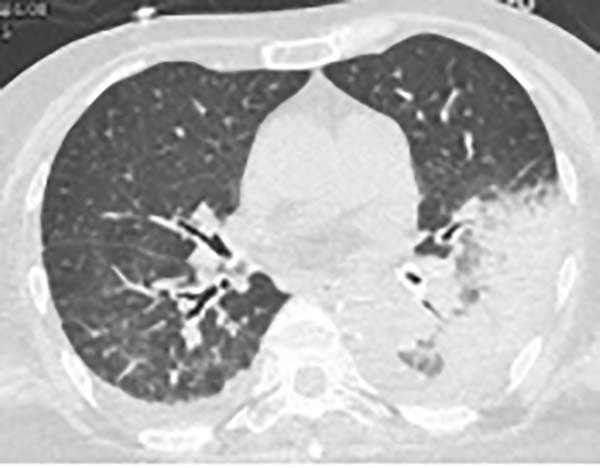

三、胸CT有哪些特点?

胸CT以炎性病变始于单侧肺下叶多见,加重后累及双侧肺叶,上下肺均可受累,主要表现为大片状实变影,可合并小片状磨玻璃影、结节影,以胸膜下分布为主,可见“支气管充气征”“细网格征”“晕征”,常伴胸腔积液,可伴淋巴结肿大。